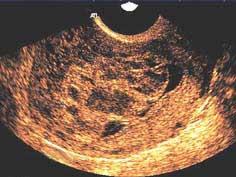

问题 女性,28岁,已婚。停经2个多月,阴道不规则出血2周,GP,妇科检查:宫颈蓝,子宫增大如孕3个多月,附件(–),尿HCG(+),做B超如图,呈“落雪状图像”改变。最可能的诊断是 ( )

选项 A、子宫内膜增殖症 B、子宫内膜炎 C、葡萄胎 D、子宫肌瘤 E、子宫内膜癌

答案 C